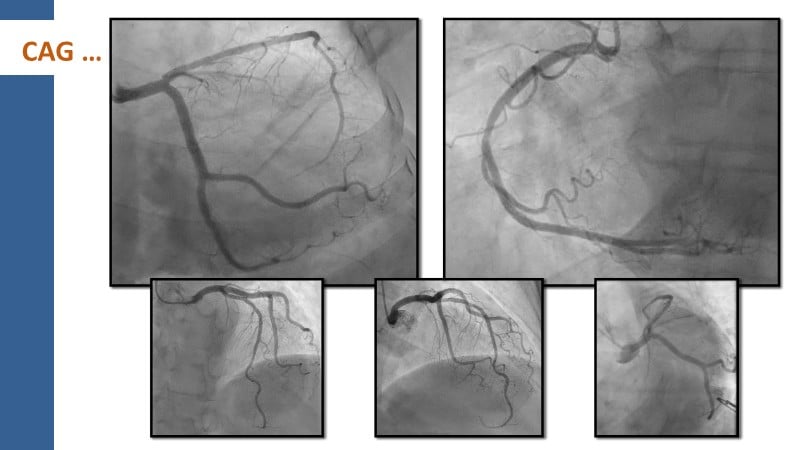

This session explores how near-infrared spectroscopy (NIRS) is redefining PCI by revealing what angiography cannot see. By identifying lipid-rich and vulnerable plaques, NIRS helps anticipate procedural risk and refine decision-making before stent implantation. The session shows how plaque composition, rather than calcium alone, can guide lesion preparation strategies, support safer stent positioning, and improve expansion. Through practical examples, it highlights how integrating NIRS with intravascular imaging and physiology moves PCI toward a more targeted, data-driven, and truly precision-based approach.

- To identify vulnerable plaques: NIRS detects lipid-rich plaques that are invisible to angiography. This allows interventionalists to anticipate complications like distal embolisation or no-reflow and adjust their approach accordingly